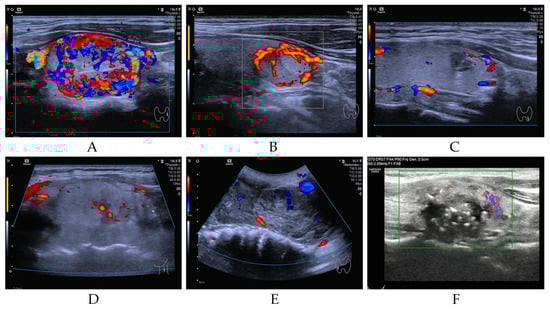

Our study cohort encompassed a total of 952 individuals diagnosed with a spectrum of thyroid neoplasms, categorized as follows: BT (n = 14, 1.47%), LRN (n = 12, 1.26%), PTC (n = 907, 95.27%), FTC (n = 5, 0.53%), PDTC&ATC (n = 9, 0.95%), and MTC (n = 5, 0.53%). As illustrated in Figure 1 (Study flow chart), all patients underwent DNA-NGS, with 919 follicular-derived tumors classified into four molecular categories: BRAF-like (n = 830, 90.3%), RAS-like (n = 36, 3.9%), high-risk (n = 25, 2.7%), and other mutations (n = 28, 3.1%). All pathological diagnoses were authenticated at the Sun Yat-sen Memorial Hospital, ensuring the accuracy of our study’s foundational data. The NGS database incorporated data extracted from 952 distinct samples, each aligning with an individual patient. Figure 2 presents representative ultrasonographic features of BT, LRN, PTC, FTC, PDTC&ATC, and medullary thyroid carcinoma (MTC).

Figure 2. Representative ultrasonographic features of BT (A), LRN (B), PTC (C), FTC (D), PDTC&ATC (E), and MTC (F).